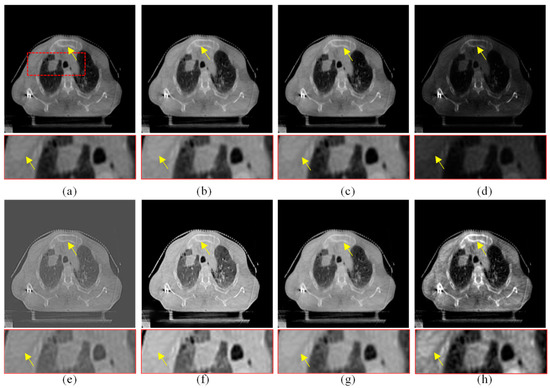

Figure 10.

Enhanced results of pair 4. (a) Source CBCT images. (b) MSR. (c) MSRCR. (d) DCP. (e) CBF. (f) RRM. (g) SMIPC. (h) Ours.

The same conclusion can also be obtained in Figure 9 and Figure 10. Especially in the enalrged region in Figure 10, our results provide a much clearer organizational structural and edge infromation, which is very helpful for disease diagnosis and treatment. Through comparison, it can be found that the rigidity informaiton in our results is more significant, the tissue edge in our results is clearer, and the contrast of the texture structure is also better than that of the comparison algorithms. The observation effect is greatly improved by our enhancement method, proving that our method can effectively enhance the CBCT images.